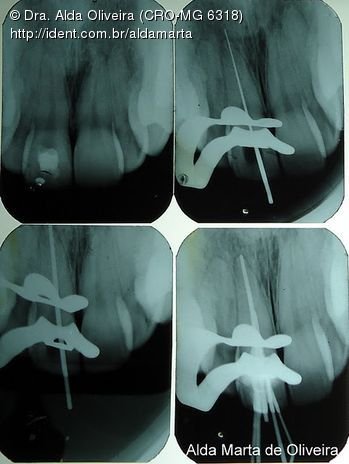

Fotos do caso

Foto 1 de 16

Um prezinho maneiro...

Além da endo, botei pino tb...

Neste caso, excepcionalmente o pino teve que ser na raiz M(vcs entenderam o motivo, não?)